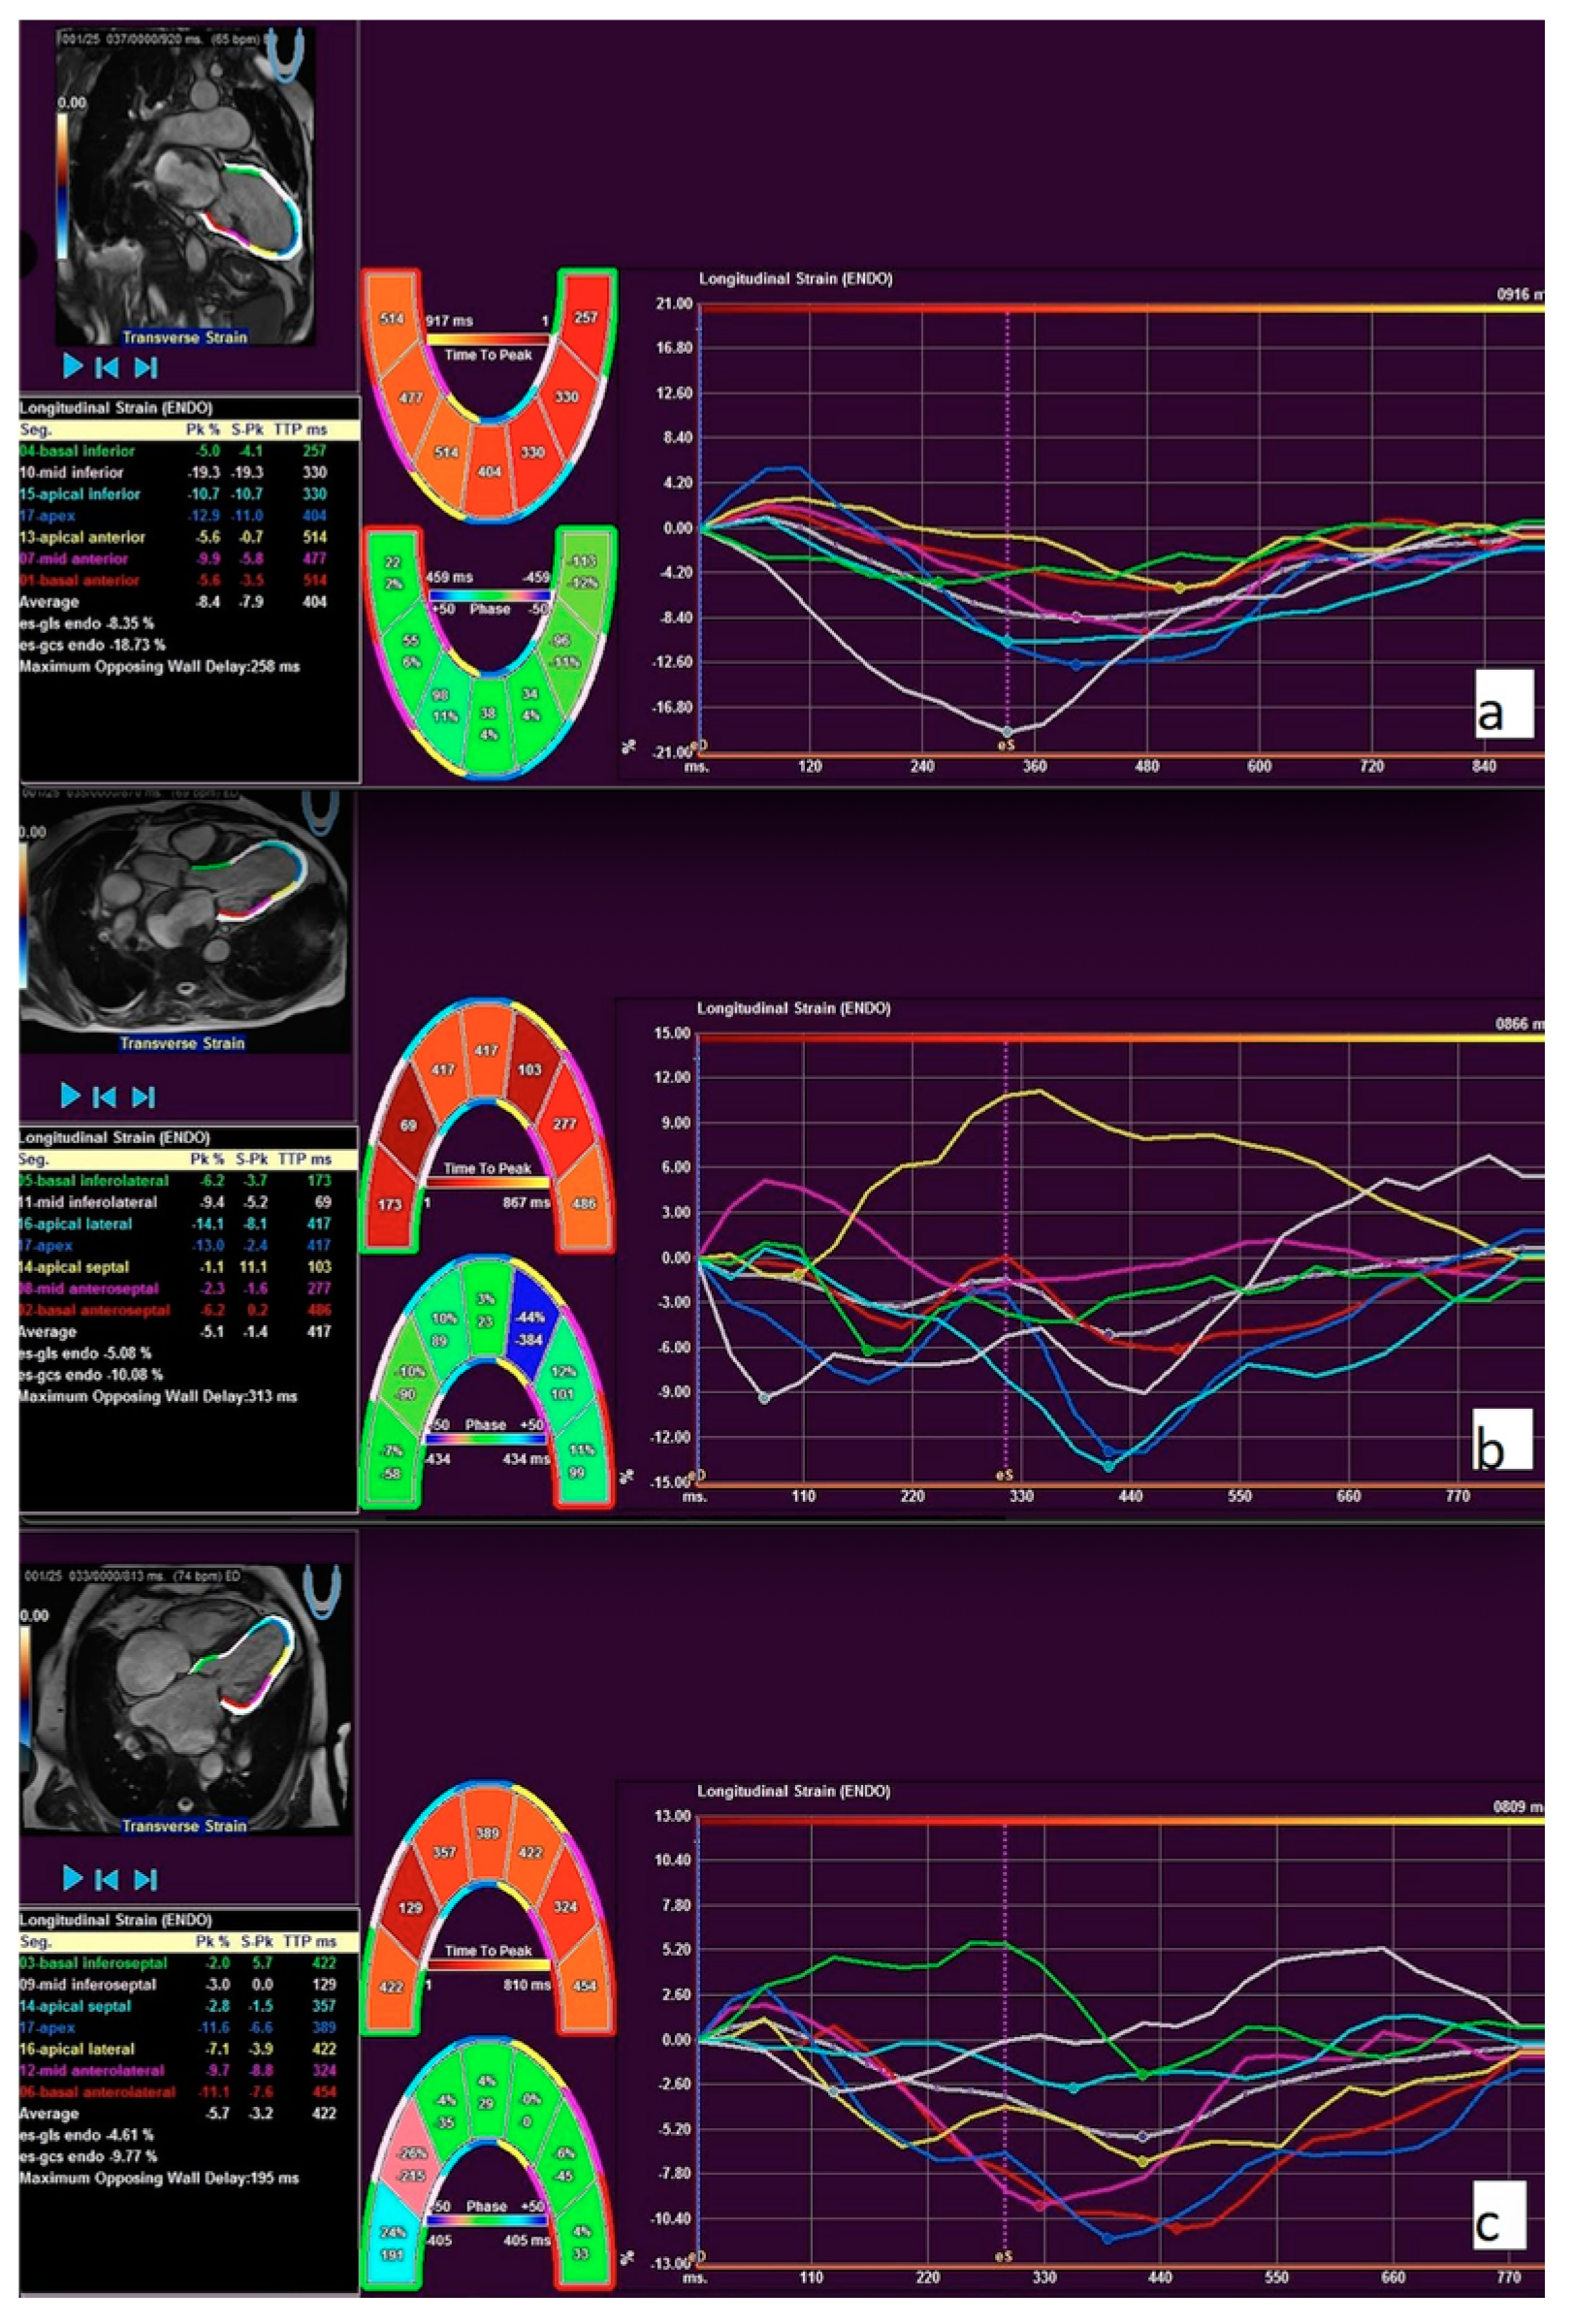

2.4. Feature Tracking Mechanical Analysis

| RV GLS (%) | −13.8 (−16.6–(−10.5)) | −14.15 (−16.68–(−11.53)) | −10.5 (−18.0–(−8.3)) | 0.134 |

| LV GLS (%) | −16.43 (−19.5–(−12.63)) | −17.61 (−19.78–(−15.11)) | −12.17 (−18.57–(−6.85)) | 0.021 |

| LV GCS (%) | −31.1 (−34.7–(−25.97)) | −31.6 (−35.82–(−26.39)) | −29.9 (−32.28–(−21.88)) | 0.224 |

| LV GLS >−14.183% | 75.6 | 77.8/86.7 | 4 (13.3)/7 (77.8) | 0.001 | 22.75 (3.432–150.811) |

| LV GLS >−14.183 | 32.184 (3.145–329.341); 0.003 |